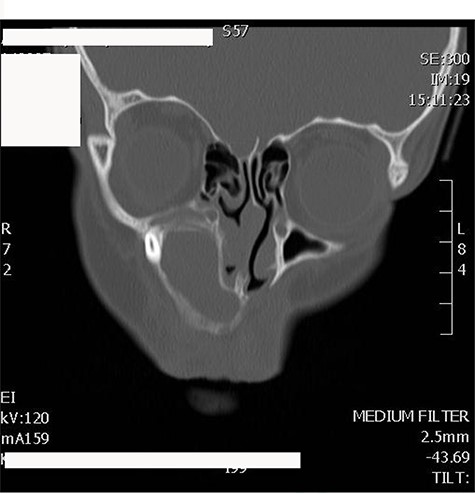

A 19-years-old male presented to otolaryngology clinic facial pain over the upper jaw area along with post-nasal discharge for 6 months. Patient gave history of recurrent sinusitis; otherwise, he is medically and surgically free with no history of trauma. Examination showed septal spur to the left side with no other significant findings. CT scan of the paranasal sinuses showed bilateral ectopic teeth and cystic lesions within both of the maxillary sinuses (Fig. 5). Patient was managed with endoscopic endonasal enucleation of the cysts and extraction of the ectopic impacted teeth through middle meatal antrostomies. Histopathology confirms the diagnosis of dentigerous cysts. Post operatively, the patient symptoms resolve completely, and she remained symptoms free over 5 years follow up.

CT scan of the paranasal sinuses showed bilateral ectopic teeth and cystic lesions within both of the maxillary sinuses.